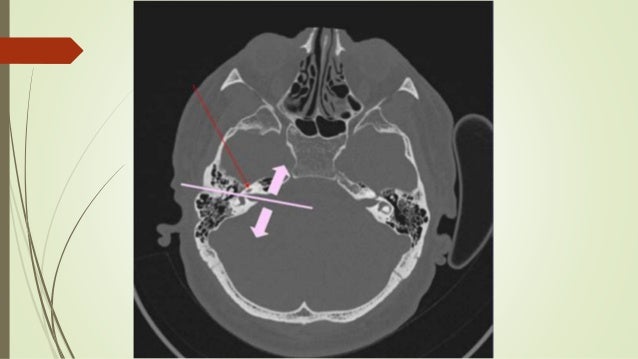

Ct Scan Temporal Bone Dr Zeeshan Ahmad

Ct scan temporal bone Dr Zeeshan Ahmad www.slideshare.net

temporal ahmad zeeshan